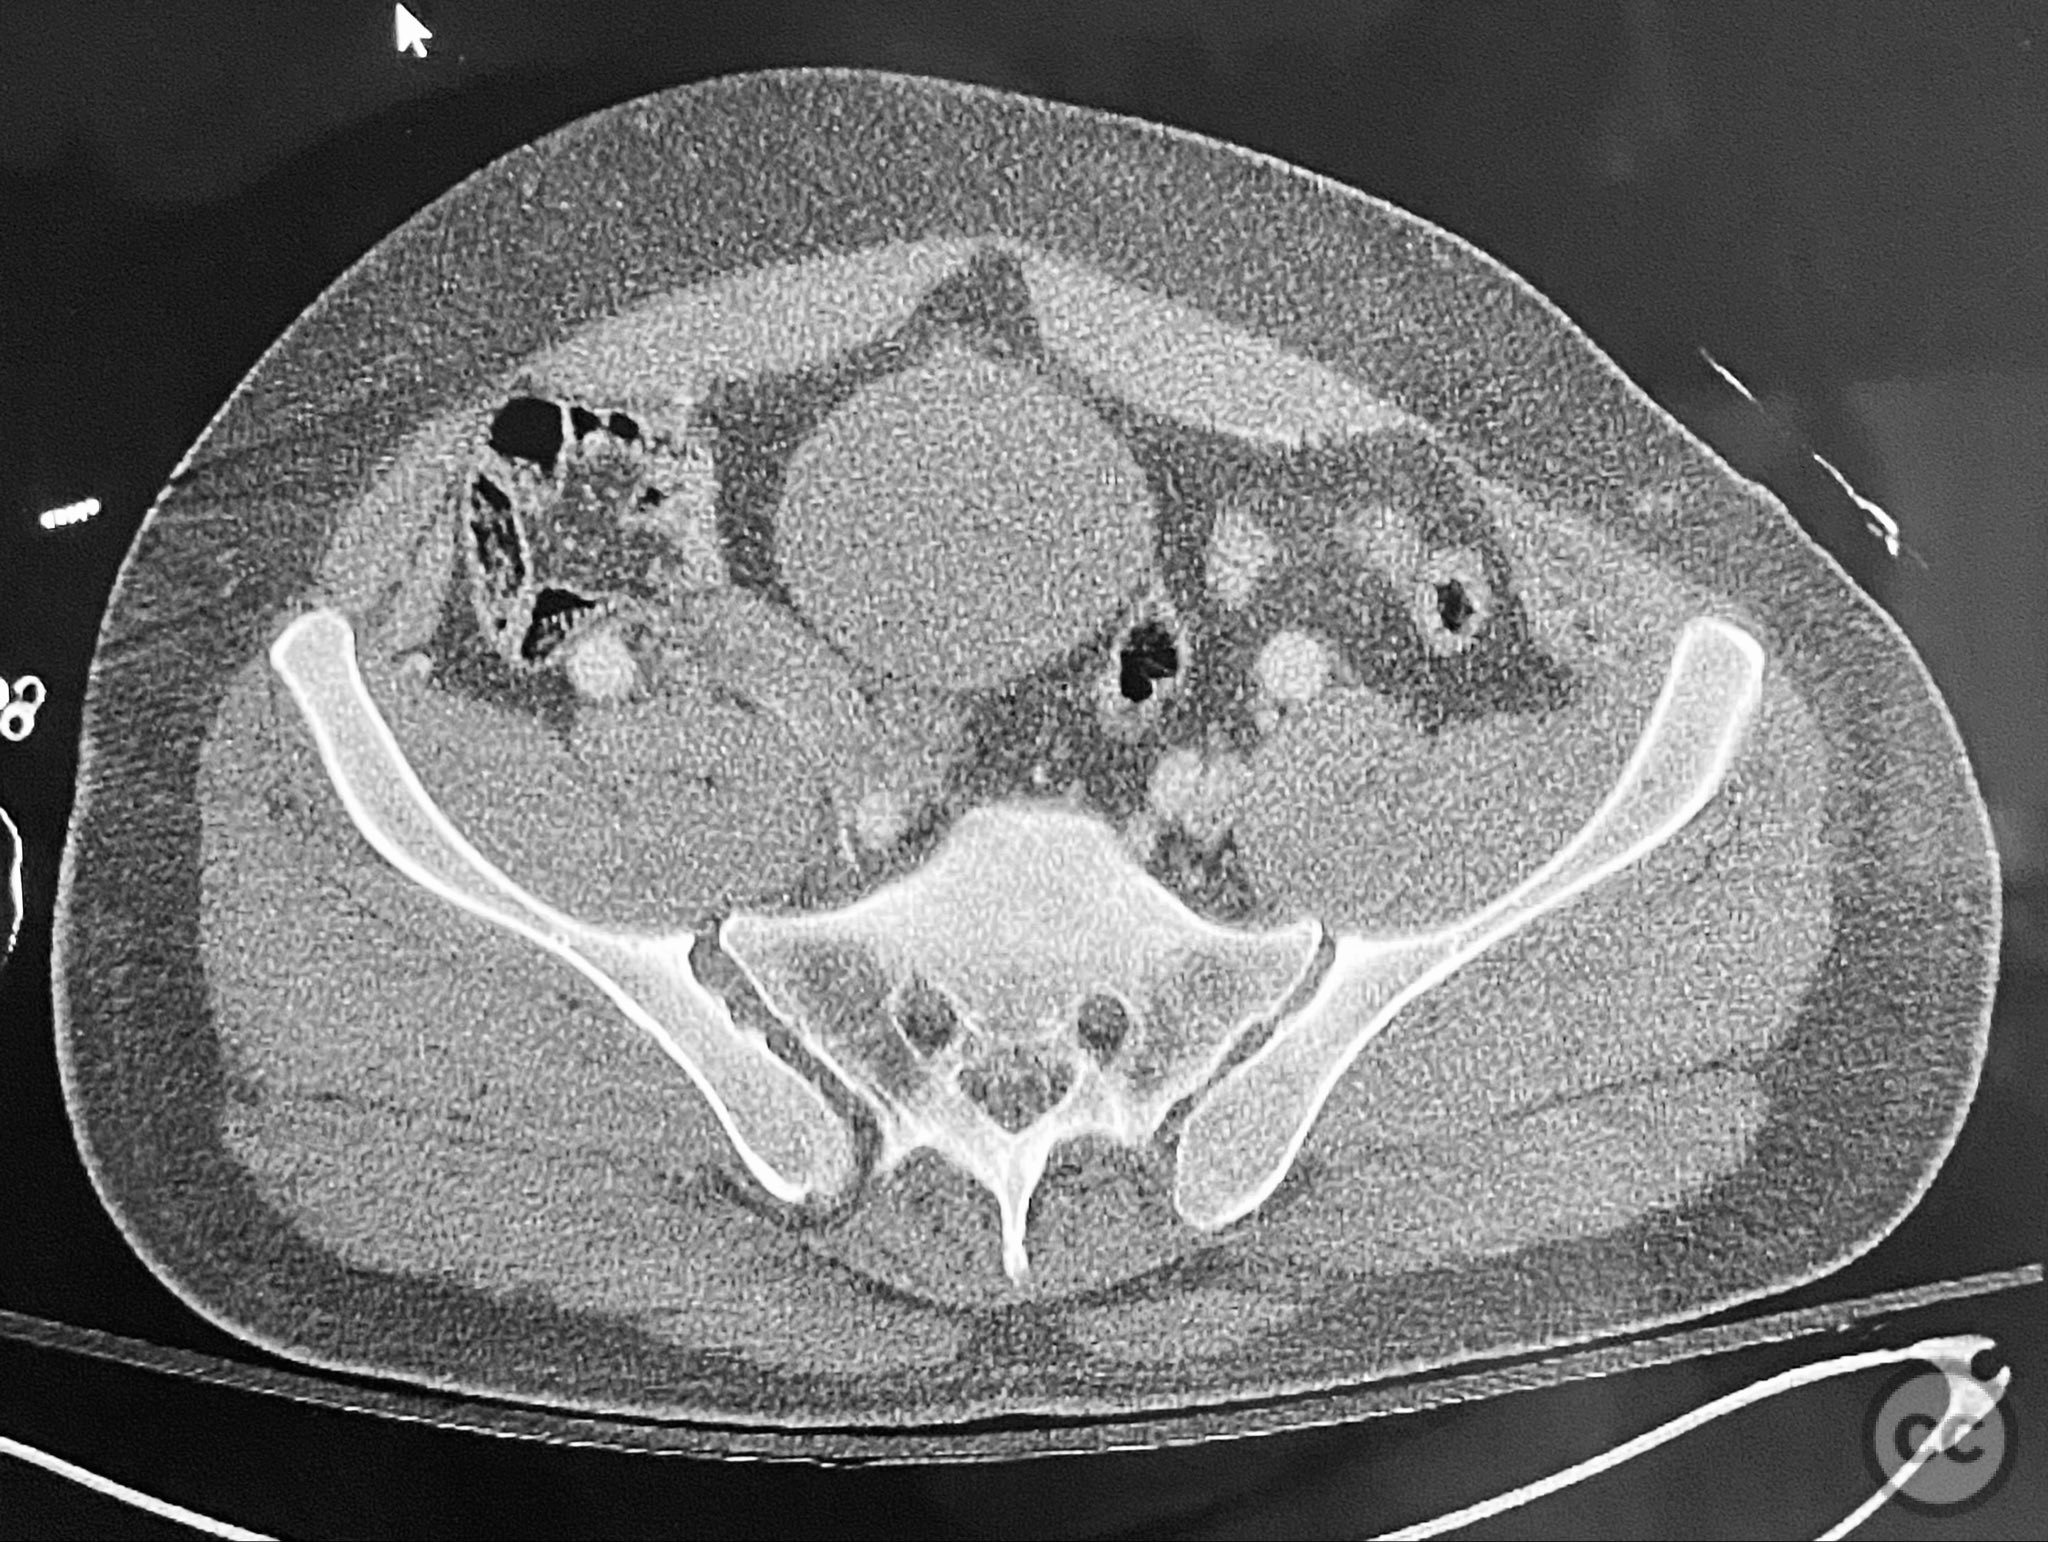

Clinical and radiological findings:  Adult male with a closed, comminuted left femoral shaft fracture and complex pelvic ring injury. Initial imaging demonstrated bilateral sacroiliac (SI) joint disruptions and a left-sided transtectal transverse acetabular fracture (Letournel-Judet: transverse type), with the fracture line exiting through the posterior wall region but without a discrete posterior wall fragment. The femoral head was displaced caudally, following the unstable distal acetabular segment, resulting in loss of congruency with the intact acetabular dome. There was also a symphyseal disruption. No associated abdominal, visceral, thoracic, cranial, or other injuries were present. Application of a circumferential pelvic binder resulted in visible changes in pelvic alignment on imaging. AO/OTA Classification: - Pelvic ring: 61-C1.3 (bilateral SI joint disruption, complete instability) - Acetabulum: 62-B1 (transverse fracture) - Femur: 32-C3 (comminuted diaphyseal fracture)

Planning remarks:  The preoperative plan involved staged management: initial resuscitation and provisional stabilization with a circumferential pelvic binder, followed by operative reduction and fixation of the pelvic ring using an anterior two-pin external fixator for SI joint compression and reduction, percutaneous iliosacral (IS) and transsacral (TS) screw fixation, and subsequent intramedullary nailing of the femur. Definitive acetabular fixation was planned via a posterior Kocher-Langenbeck approach in the prone position.